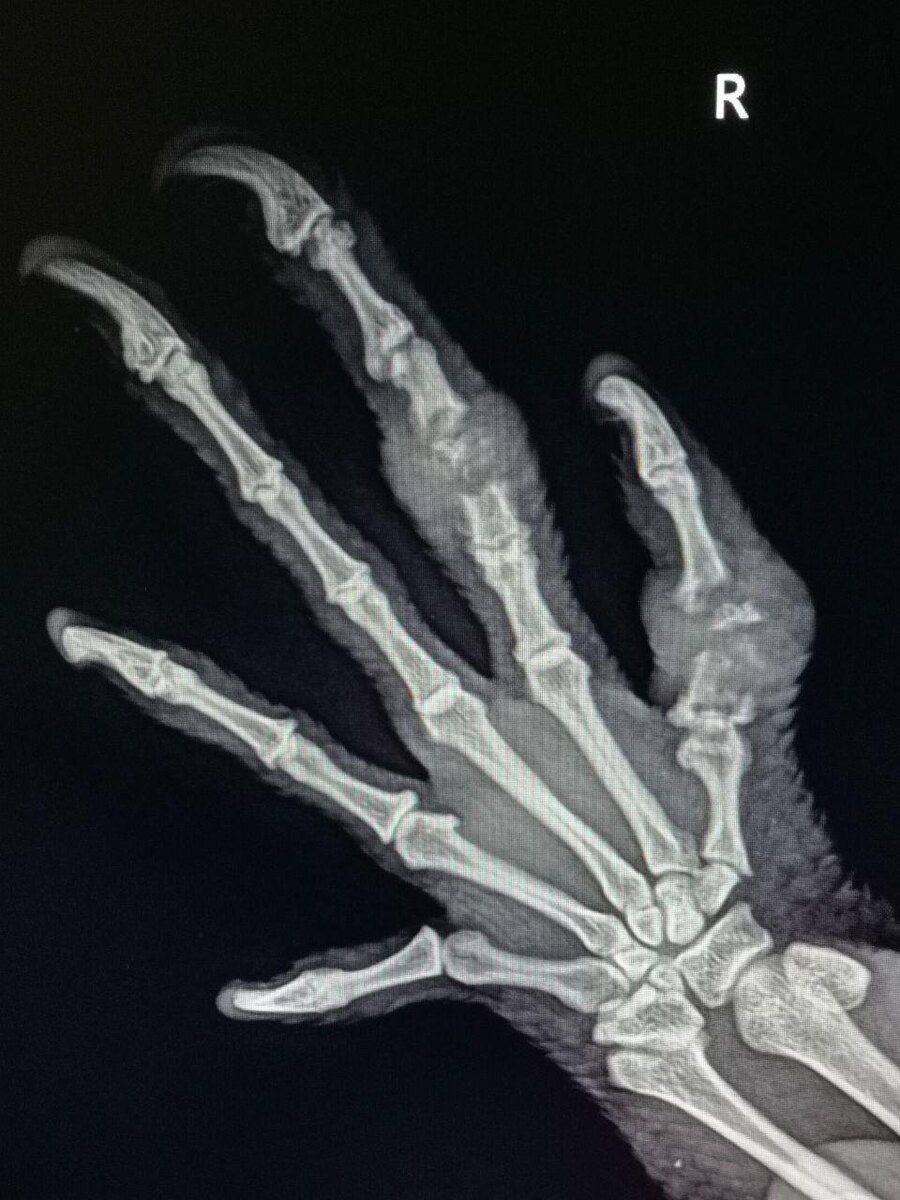

Привет, друзья! Сегодня расскажу вам о необычной новости из мира животных. В Москве прооперировали огромную игуану по имени Изумрудик, которая сломала пальцы в драке со своим отражением.

Изумрудик, полутораметровый ящер, увидел себя в зеркале и решил, что перед ним соперник. В результате — два сломанных пальца и необходимость операции под наркозом. Но не волнуйтесь, операция прошла успешно, и сразу после неё Изумрудик попытался сбежать. Сейчас он восстанавливается дома.